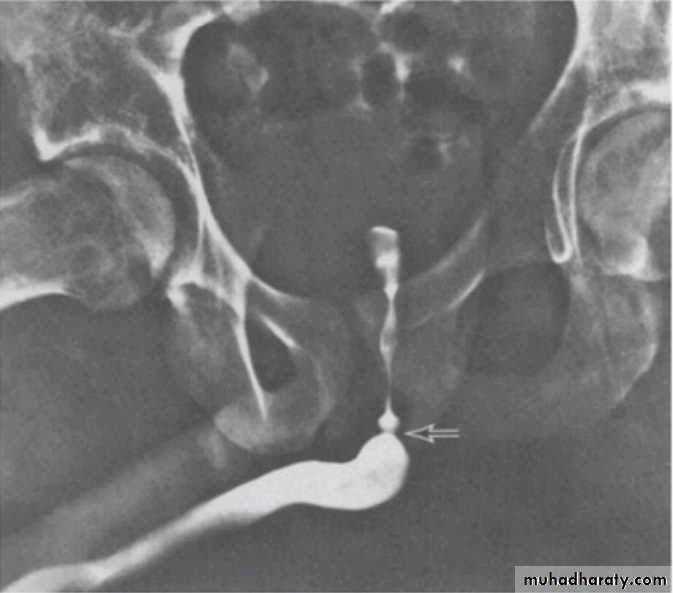

Voiding cystourethrogram

POSTERIOR URETHRAL VALVE

Voiding cystourethrogram.Excretory urogram.